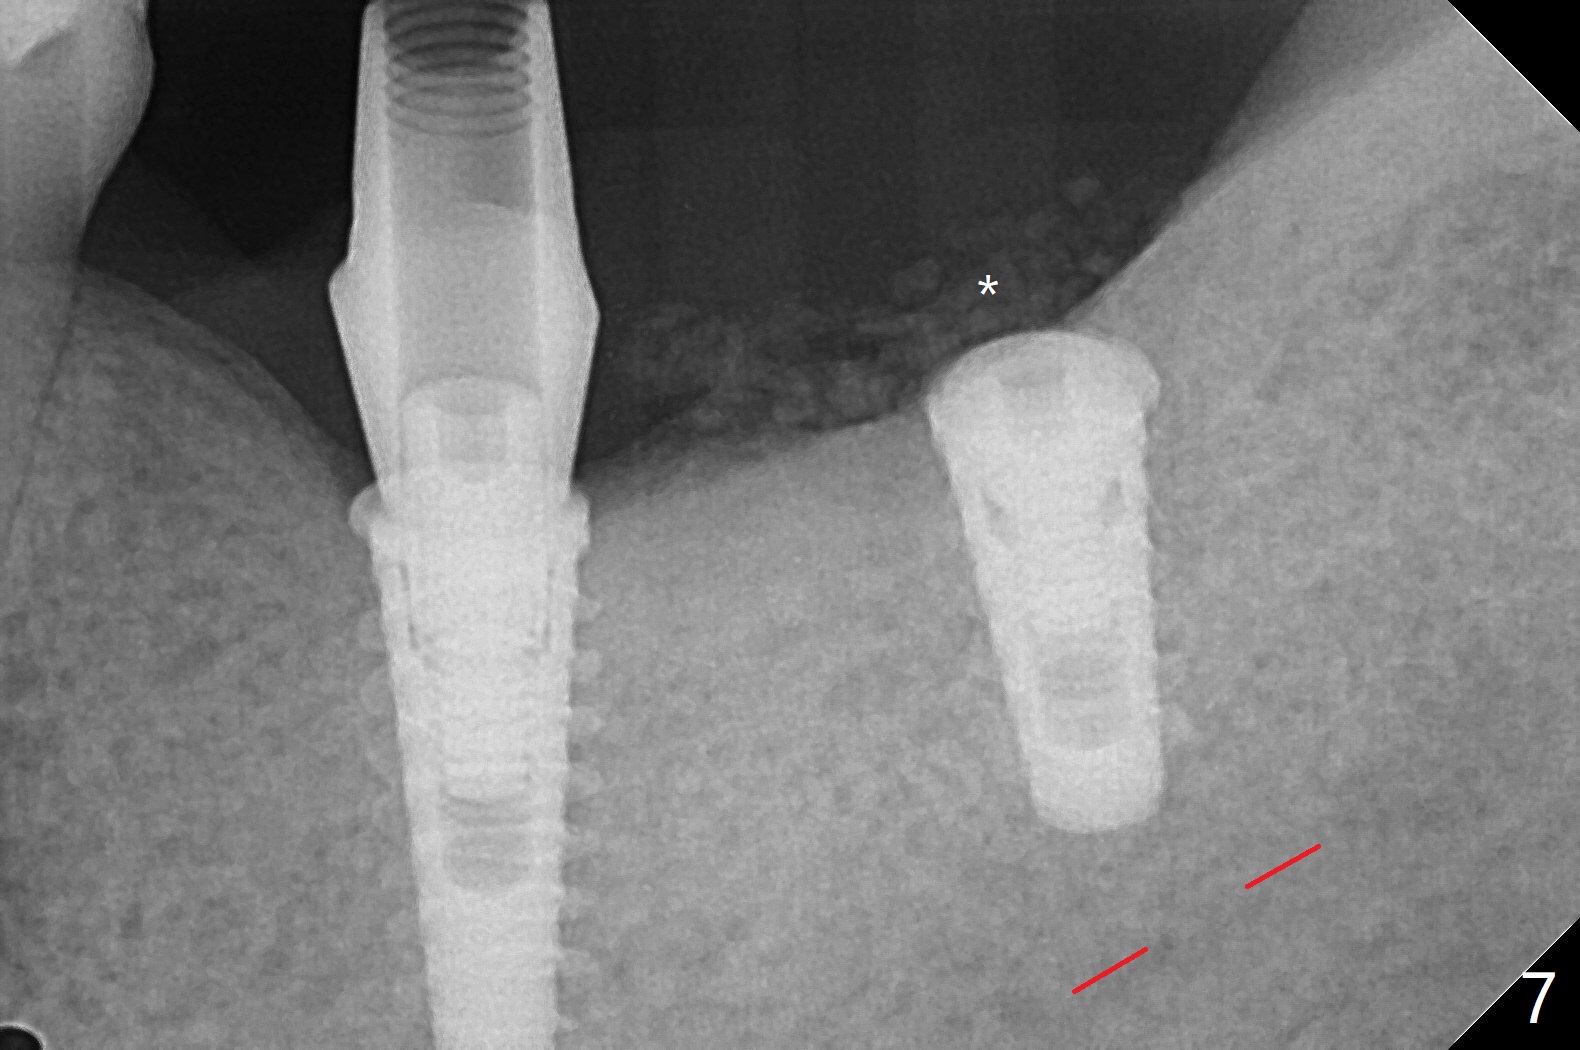

Following placement of a 4.5x11 mm implant at #19 (14 months post guide fabrication), a fixture anchor pin is placed. With stable guide, it is much easier to finish osteotomy and implant placement at #18 (Fig.1). Since the patient is nervous and sensitive to drilling, a shorter implant is placed (7 mm instead of 9 mm vs. 8.5 mm drill). The stability is unaffected because of the dense bone. After use of 5.5 mm profile drill, healing abutments (5.5x3 and 5.5x4 mm) are placed without interference. There is crestal bone loss in 3 months (Fig.2, as compared to Fig.1). Since there is more space apical to the pair abutment at #19 than that at #18, incomplete abutment seating is suspected at #19. More X-ray will be taken (Fig.3,4). In fact, it is not necessary. The space differential is also noted with healing abutments in Fig.1. BW cannot tell whether the abutment at #19 is seated or not (Fig.3). When the abutment is changed at #19 with 30 Ncm torque, the space differential remains (Fig.4, as compared Fig.2) and must be normal. The shorter implant at #18 appears not osteointegrate, since the patient feels pain when the abutment is torqued at 15 Ncm. The patient returns for temporary crown contour adjustment 1-2 weeks later. The implant at #18 is removed when the abutment screw is untightened 7 months postop; Cortical bone is placed with 6 month membrane (Fig.5). Three months later, incision will be made with reuse of the guide with fixture pin at #19. If a 4.5x9 mm implant cannot be placed, bury a short and/or narrow implant. Impression will be taken for #19 soon. In fact fixture pin cannot be seated. It appears that cancellous bone reforms, presumably low density. Underdrilling is conducted in diameter. The torque is high, but normal drilling is not carried out. The former implant exfoliated probably due to compression necrosis. The new implant is not completely seated, partially out of fear of being close to the Inferior Alveolar Canal (Fig.6). After cortical plate perforation, allograft is placed (Fig.7 *), followed by buccal flap release (periosteum underscored). In fact the implant does not have enough clearance from the Canal (red dashed line: the superior border of the Canal). The abutment at #19 returns to hold periodontal dressing in place. The implant is buried in the bone except lingual 4 months postop (Fig.8,9).